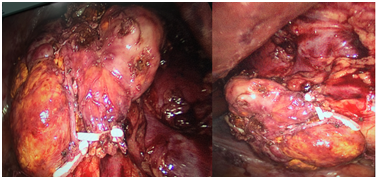

A 32 age women underwent a regular routine test 1 month ago that ultrasound showed a mass in the right adrenal gland. She denied any known medical conditions, such as hyperaldosteronism, hypertension and hypercortisolism. Further examination was taken in our hospital. The contrast-enhanced CT identified a quasi-circular nodular lesion in the right adrenal gland, measuring 6x6.5cm and displaying heterogeneous with mottling and spotty dense calcification on the edge of the mass. The margin of lesion was clear and presented 46 HU in plain scan and 68-113 HU in the enhancement. The tumor surrounded the right renal vein and part of postcava, but didn’t narrow the vessels (Figure 1). All of functional laboratory evolution showed negative including blood testing for catecholamines (epinephrine and norepinephrine) and their metabolites (metanephrine in serum and VMA in a 24-hour urine sample), free cortisol and ACTH (adrenocorticotropic hormone) in serum and plasma testing for renin-angiotensin-aldosterone under recumbent and upright state. A laparoscopic right adrenalectomy was performed (Figure 2) and postoperative pathology revealed a right ganglioneuroma. Immunohistochemistry showed S-100, CD56, Syn and CgA staining are positive Figure 3 & 4). After one year follow-up, the patient has not had any local recurrence and distant metastasis.

Figure 2 A mass with intact capsule and partial adrenal tissue was removed by laproscopic surgery.